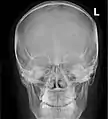

X-ray images and illustrations

Paranasal sinuses radiograph (occipitofrontal)